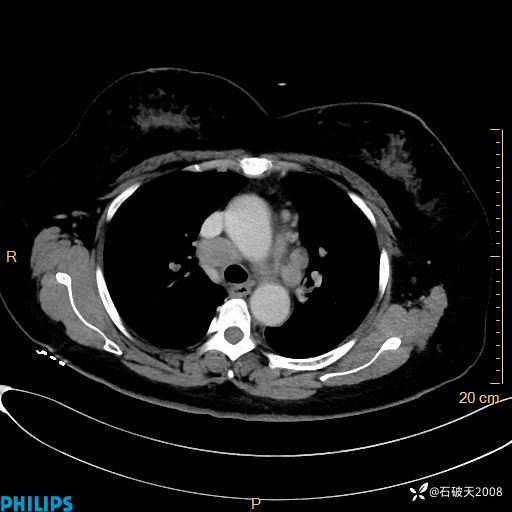

静脉期